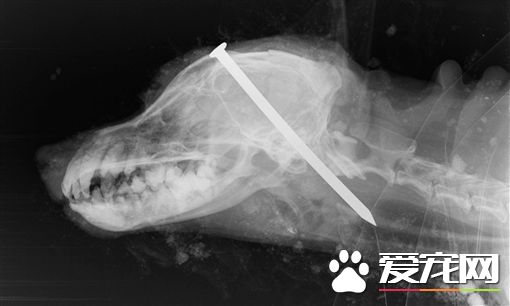

为了省钱,竟然做出这等惨忍行为,太可恶了!近日英国一名饲主,为了省安乐死的前,竟然使用铁钉刺穿狗的头部后活埋。事后被人发现将它救出,但已回天乏术了。

据外媒《守护者》(Guardian),英国一只名叫史盖(Scamp)的老狗,因年纪大多处病痛,饲主决定将它安乐死,却无力支付300英镑费用。竟然找来朋友帮忙,用长钉硬生生钉进史盖的脑中后活埋。事后史盖不断从土里发出叫声,被附近一对夫妇听见救出,送兽医急救,但还是来不及了。

兽医表示史盖头部至少受到6次重击,是他30年来见过最惨酷的虐待动物行为。事后饲主和朋友被逮,被控虐待动物罪成立囚行4个月,让当地爱狗人士表示我很高兴他们受到监禁判决,但此行为这惩罚还不够。 |